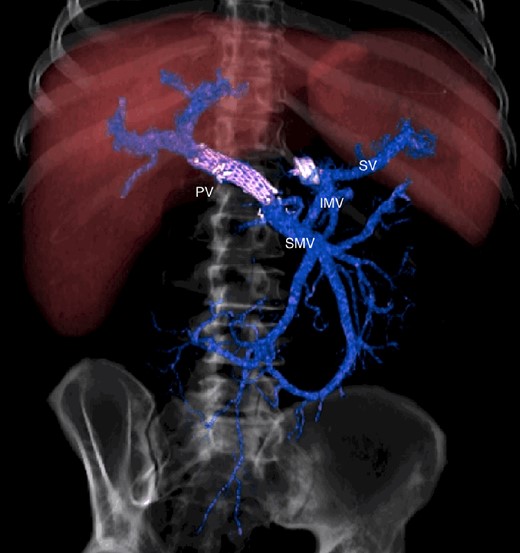

The abdominal exploration was difficult due to significant inflammatory adhesions, which can be attributed to the presence of a pancreatic fistula and the delay of relaparotomy. There was no bleeding observed within the abdominal cavity, and no bleeding was seen from the multitubular drain during the exploration. We hypothesized that the bleeding was of venous origin caused by drain-induced recurrent erosion of peripancreatic vessels, resulting in intermittent bleeding, and that removing drains could help in attaining venous hemostasis. As a result, it was decided to remove the drains. However, this resulted in a significant hemorrhage via the drain orifice. Due to failure to identify the exact origin of bleeding and without the possibility of completion pancreatectomy, we performed a damage control procedure by packing through the drain orifice. This successfully stopped the bleeding. A postoperative CT scan located the packing sponges anterior to the spleno-mesenteric confluence (SMC) (Fig. 2). A percutaneous transhepatic portography showed an irregular aspect of the SMC, without thrombi or contrast extravasation (Fig. 3). After consulting with the interventional radiology team, we placed a cover stent (Fluency™ Bard, Murray Hill, USA) in the SMC (Fig. 4). Two days later, we removed the packs, and a massive hemorrhage recurred, necessitating a new packing. The stent was not seen on a subsequent CT scan. We then performed an endovascular procedure to exclude the segment of the irregular SMC. An Amplatzer™ vascular plug (Abbott Vascular, Santa Clara, USA) was placed in the splenic vein, extending distally to just surpass the inferior mesenteric vein (IMV) insertion (Fig. 5). A cover stent was subsequently deployed in the portal vein, extending distally to the superior mesenteric vein. This allowed for the exclusion of the splenic vein segment that lies between the inferior mesenteric vein insertion point and the spleno-mesenteric confluence (Fig. 5). The packing sponges were removed 10 days later without bleeding recurrence, and the patient finally showed clinical improvement. After 3 years, the stent was visible and permeable on a follow-up CT scan. The scan showed development of venous collaterals, which drain the distal splenic vein and inferior mesenteric vein through the lesser omentum (Fig. 6).

CT scan after relaparotomy located the packs used for hemorrhage control anterior to the confluence of the portal vein and splenic vein. PV portal vein, SV splenic vein.